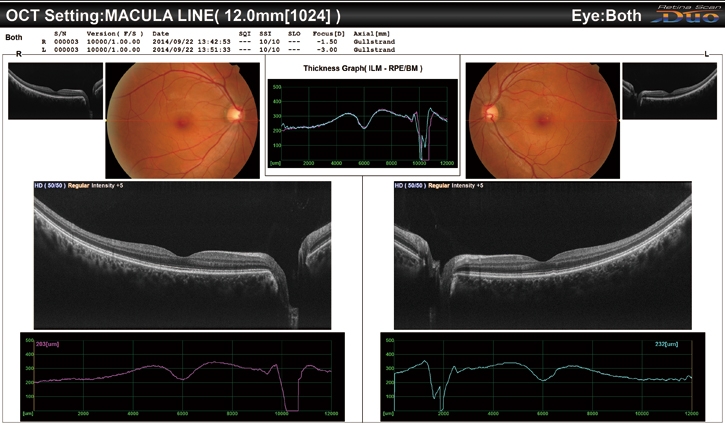

廣域掃描(12 x 9 mm)/ 廣域標(biāo)準(zhǔn)化數(shù)據(jù)庫(9 x 9 mm)

利用RS-330,可在黃斑中心進(jìn)行12 x 9 mm廣域成像。9 x 9 mm標(biāo)準(zhǔn)化數(shù)據(jù)庫提供了彩色編碼圖,該圖說明了在正常眼睛中,患者的黃斑厚度分布范圍。